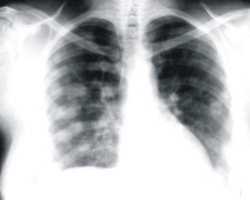

Los experimentos fueron realizados en ratones, en los cuales se evidenció el potencial terapéutico de los inhibidores de la enzima PARP, una molécula clave en la reparación de los daños inducidos sobre el ADN, cuyo uso reduce por sí solo la presencia de focos de metástasis pulmonar en aproximadamente un 90%, un efecto antimetastásico inédito en el cáncer de piel tipo melanoma.